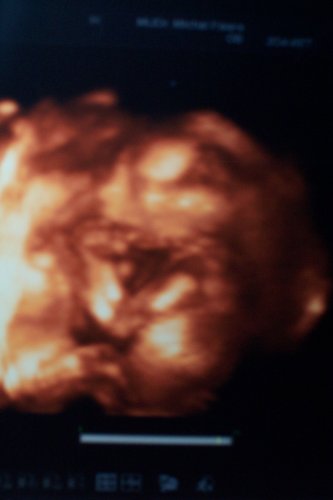

Denisa2

•  31 fotek